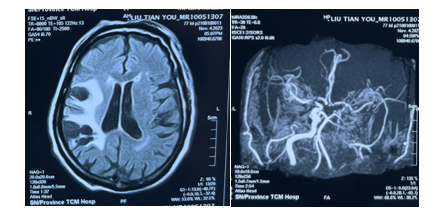

患者77岁男性,以“头晕伴行走不稳10余年”收住我院脑病一科,入院检查头颅MRI+MRA提示:右侧颞、额、顶叶脑梗赛并软化灶形成,右侧侧脑室旁及半卵圆中心多发腔隙性脑梗死,右侧颈内动脉重度狭窄,右侧大脑中动脉、前动脉全程纤细、浅淡,建议DSA进一步检查。